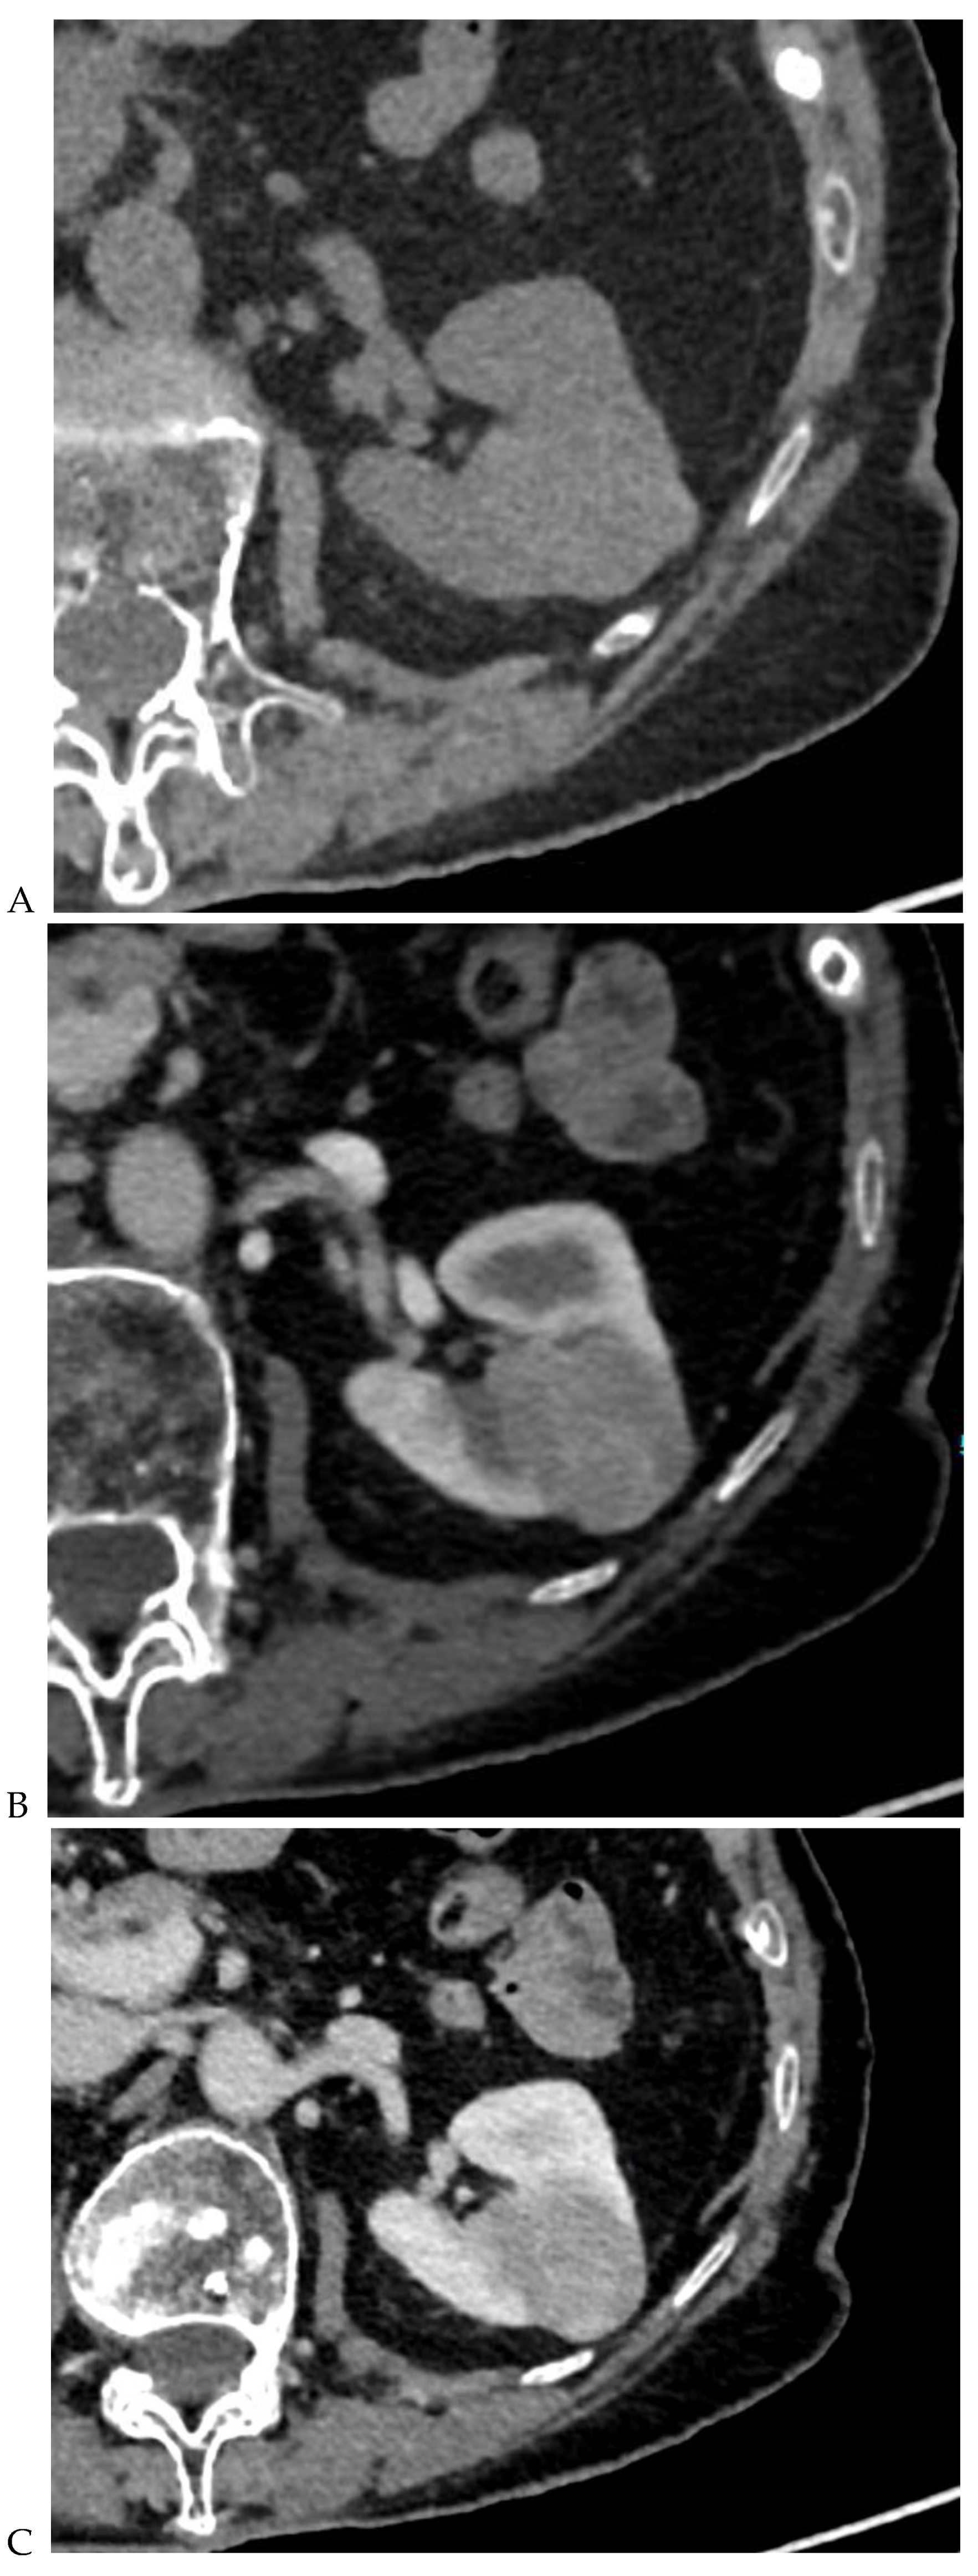

Figure 4.

Multiphasic CT enhancement of a papillary renal cell carcinoma in the middle part of the right kidney of a 63-year-old woman. (A) Mean unenhanced attenuation was 35 HU. (B) Mean corticomedullary phase attenuation was 45 HU. (C) Mean nephrographic phase attenuation was 59 HU. (D) Mean excretory phase attenuation was 65 HU.

Along with unenhanced images, enhancement on multiphasic CT provides a simple, noninvasive means of suggesting the histologic type of a renal mass. It is defined by an increase of 20 HU or more between precontrast and contrast-enhanced images [11]. In daily practice, an enhancement of <10 HU is considered to be characteristic of a cyst, 10–19 HU of an indeterminate mass, and >20 HU suggestive of a renal tumor. Young et al. [9] showed that the mean enhancement of clear cell RCC (Figure 1) was significantly greater than that of oncocytoma (Figure 2) and chromophobe RCC (Figure 3) in the cortico-medullary and excretory phases, and significantly greater than that of papillary RCC (Figure 4) in the cortico-medullary, nephrographic, and excretory phases. In their series, the mean attenuation values during the corticomedullary phase were 125.0 HU for RCCs, 106.0 HU for oncocytomas, 53.6 HU for papillary RCCs, and 73.8 HU for chromophobe RCCs. However, this quantitative information does not necessarily translate into clinically meaningful measures in daily practice due to the variability and overlap in HU measurements. In a recently published study of 87 patients with 93 pathologically proven papillary RCCs [31], most papillary RCCs presented as a hypovascular, circumscribed, solid renal mass; a few (17%) papillary RCCs presented as the newly defined Bosniak class IIF subtype.